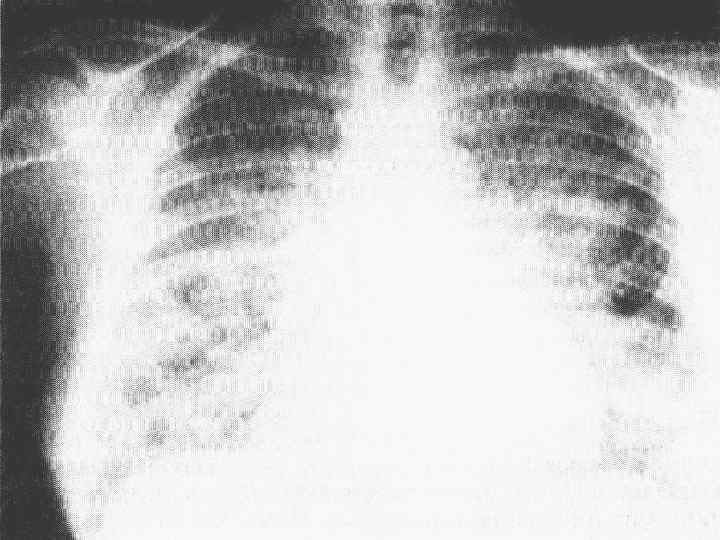

Синдром Пурчера при жировой эмболии Синдром Пурчера при жировой эмболии